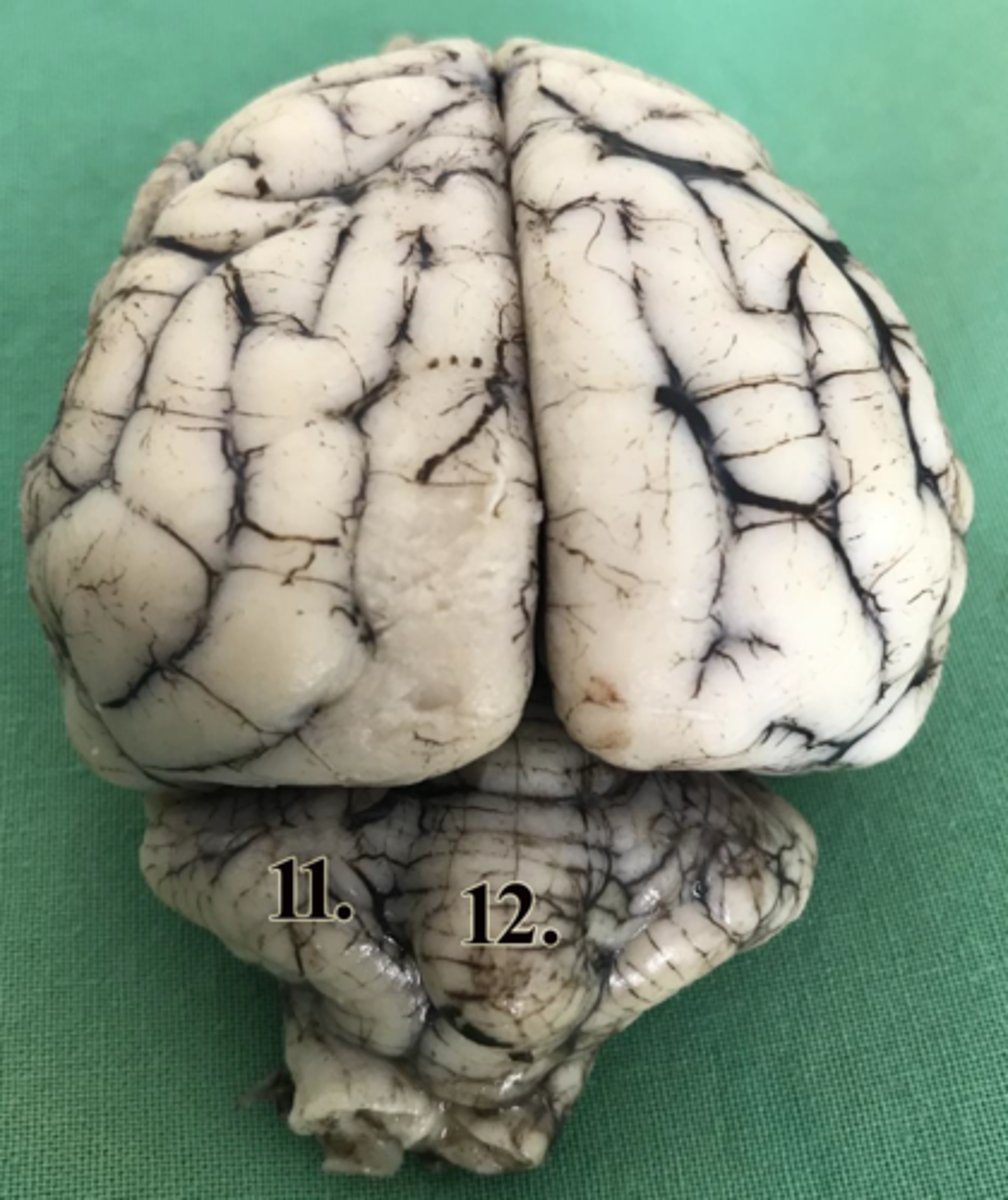

hemispherium cerebelli

11

vermis

12